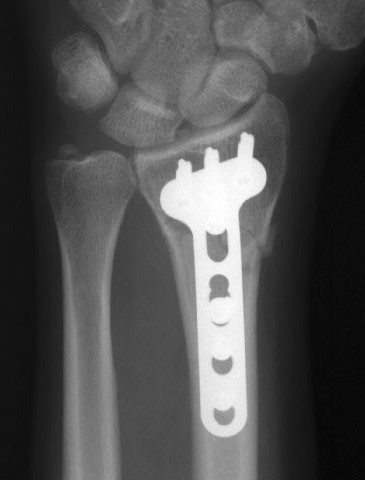

- различные виды накостного и внутрикостного остеосинтеза костей кисти и предплечья с использованием импортных и лучших представителей отечественных имплантов;

- корригирующие операции при лучевой и локтевой косорукости (неправильно сросшиеся переломы луча в типичном месте);